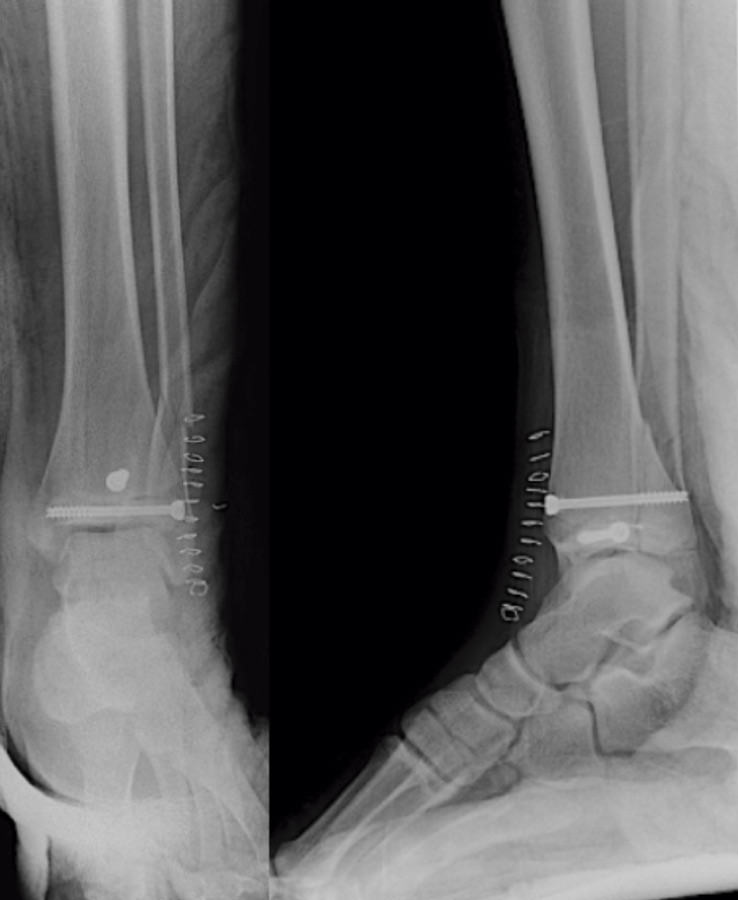

Se trata de un varón de 13 años de edad que acude a urgencias tras sufrir una caída y con eversión forzada del tobillo jugando al fútbol. A la exploración, presentaba inflamación en todo el tobillo izquierdo (región anterior y ambos maléolos) sin déficit neurovascular. En la radiografía simple se observó una fractura epifisiolisis de tipo IV (Figura 1).

Figura 1. Radiografía: epifisiolisis de tipo IV asociada a fractura de tercio distal de peroné.